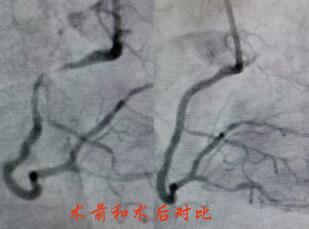

造影提示陶奶奶冠脈病情較重,左主干+三支病變,屬于非常復(fù)雜也極為危險(xiǎn)的冠脈病變。經(jīng)過心內(nèi)科介入團(tuán)隊(duì)和家屬的反復(fù)溝通,立即對陶奶奶的右冠進(jìn)行了支架置入,術(shù)后陶奶奶的胸痛很快緩解,并經(jīng)過數(shù)天的后續(xù)治療,順利出院。

春節(jié)剛過,陶奶奶的孩子們帶著陶奶奶再次來到了江寧中醫(yī)院心內(nèi)科準(zhǔn)備拆除這顆潛在的“致命炸彈”。韋鋒主任反復(fù)研究陶奶奶的前期手術(shù)影像,心中擬定著多個(gè)手術(shù)方案。經(jīng)過充分準(zhǔn)備,2月15日,韋鋒主任再次為陶奶奶進(jìn)行了介入手術(shù)。術(shù)中通過血管內(nèi)超聲(IVUS)精細(xì)、準(zhǔn)確評估陶奶奶的冠脈病變情況,發(fā)現(xiàn)陶奶奶的左主干最小管腔面積僅僅3.7mm2,;前降支近段全程鈣化,最嚴(yán)重處呈270度的環(huán)形鈣化,最小管腔面積僅僅2.1mm2;回旋支開口正常,回旋支近端最小管腔面積1.8mm2。韋鋒主任根據(jù)IVUS的結(jié)果,改變了原來擬定的DKCRUSH術(shù)式,決定采用藥物球囊和藥物涂層支架相結(jié)合的方式處理病變(LCX藥物球囊,LM-LAD植入支架),經(jīng)過近2個(gè)小時(shí)的手術(shù),陶奶奶的冠脈血管又“完美”地回來了。